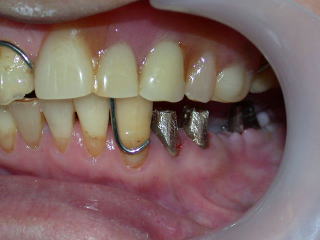

インプラント植立1週間後の平成20年2月29日に縫合糸を抜いて型取りをします。

事前にインプラント植立する左側の咬合負担を軽くするために、上と右下の義歯の咬み合わせを高くしてあります。

歯肉の形状は、歯肉がコブ状で不整形ですが、いずれ平坦で滑らかな形状となります。

上下の補綴スペース(上部構造物:セラミックスや金属の冠の入る隙間)を確認します。